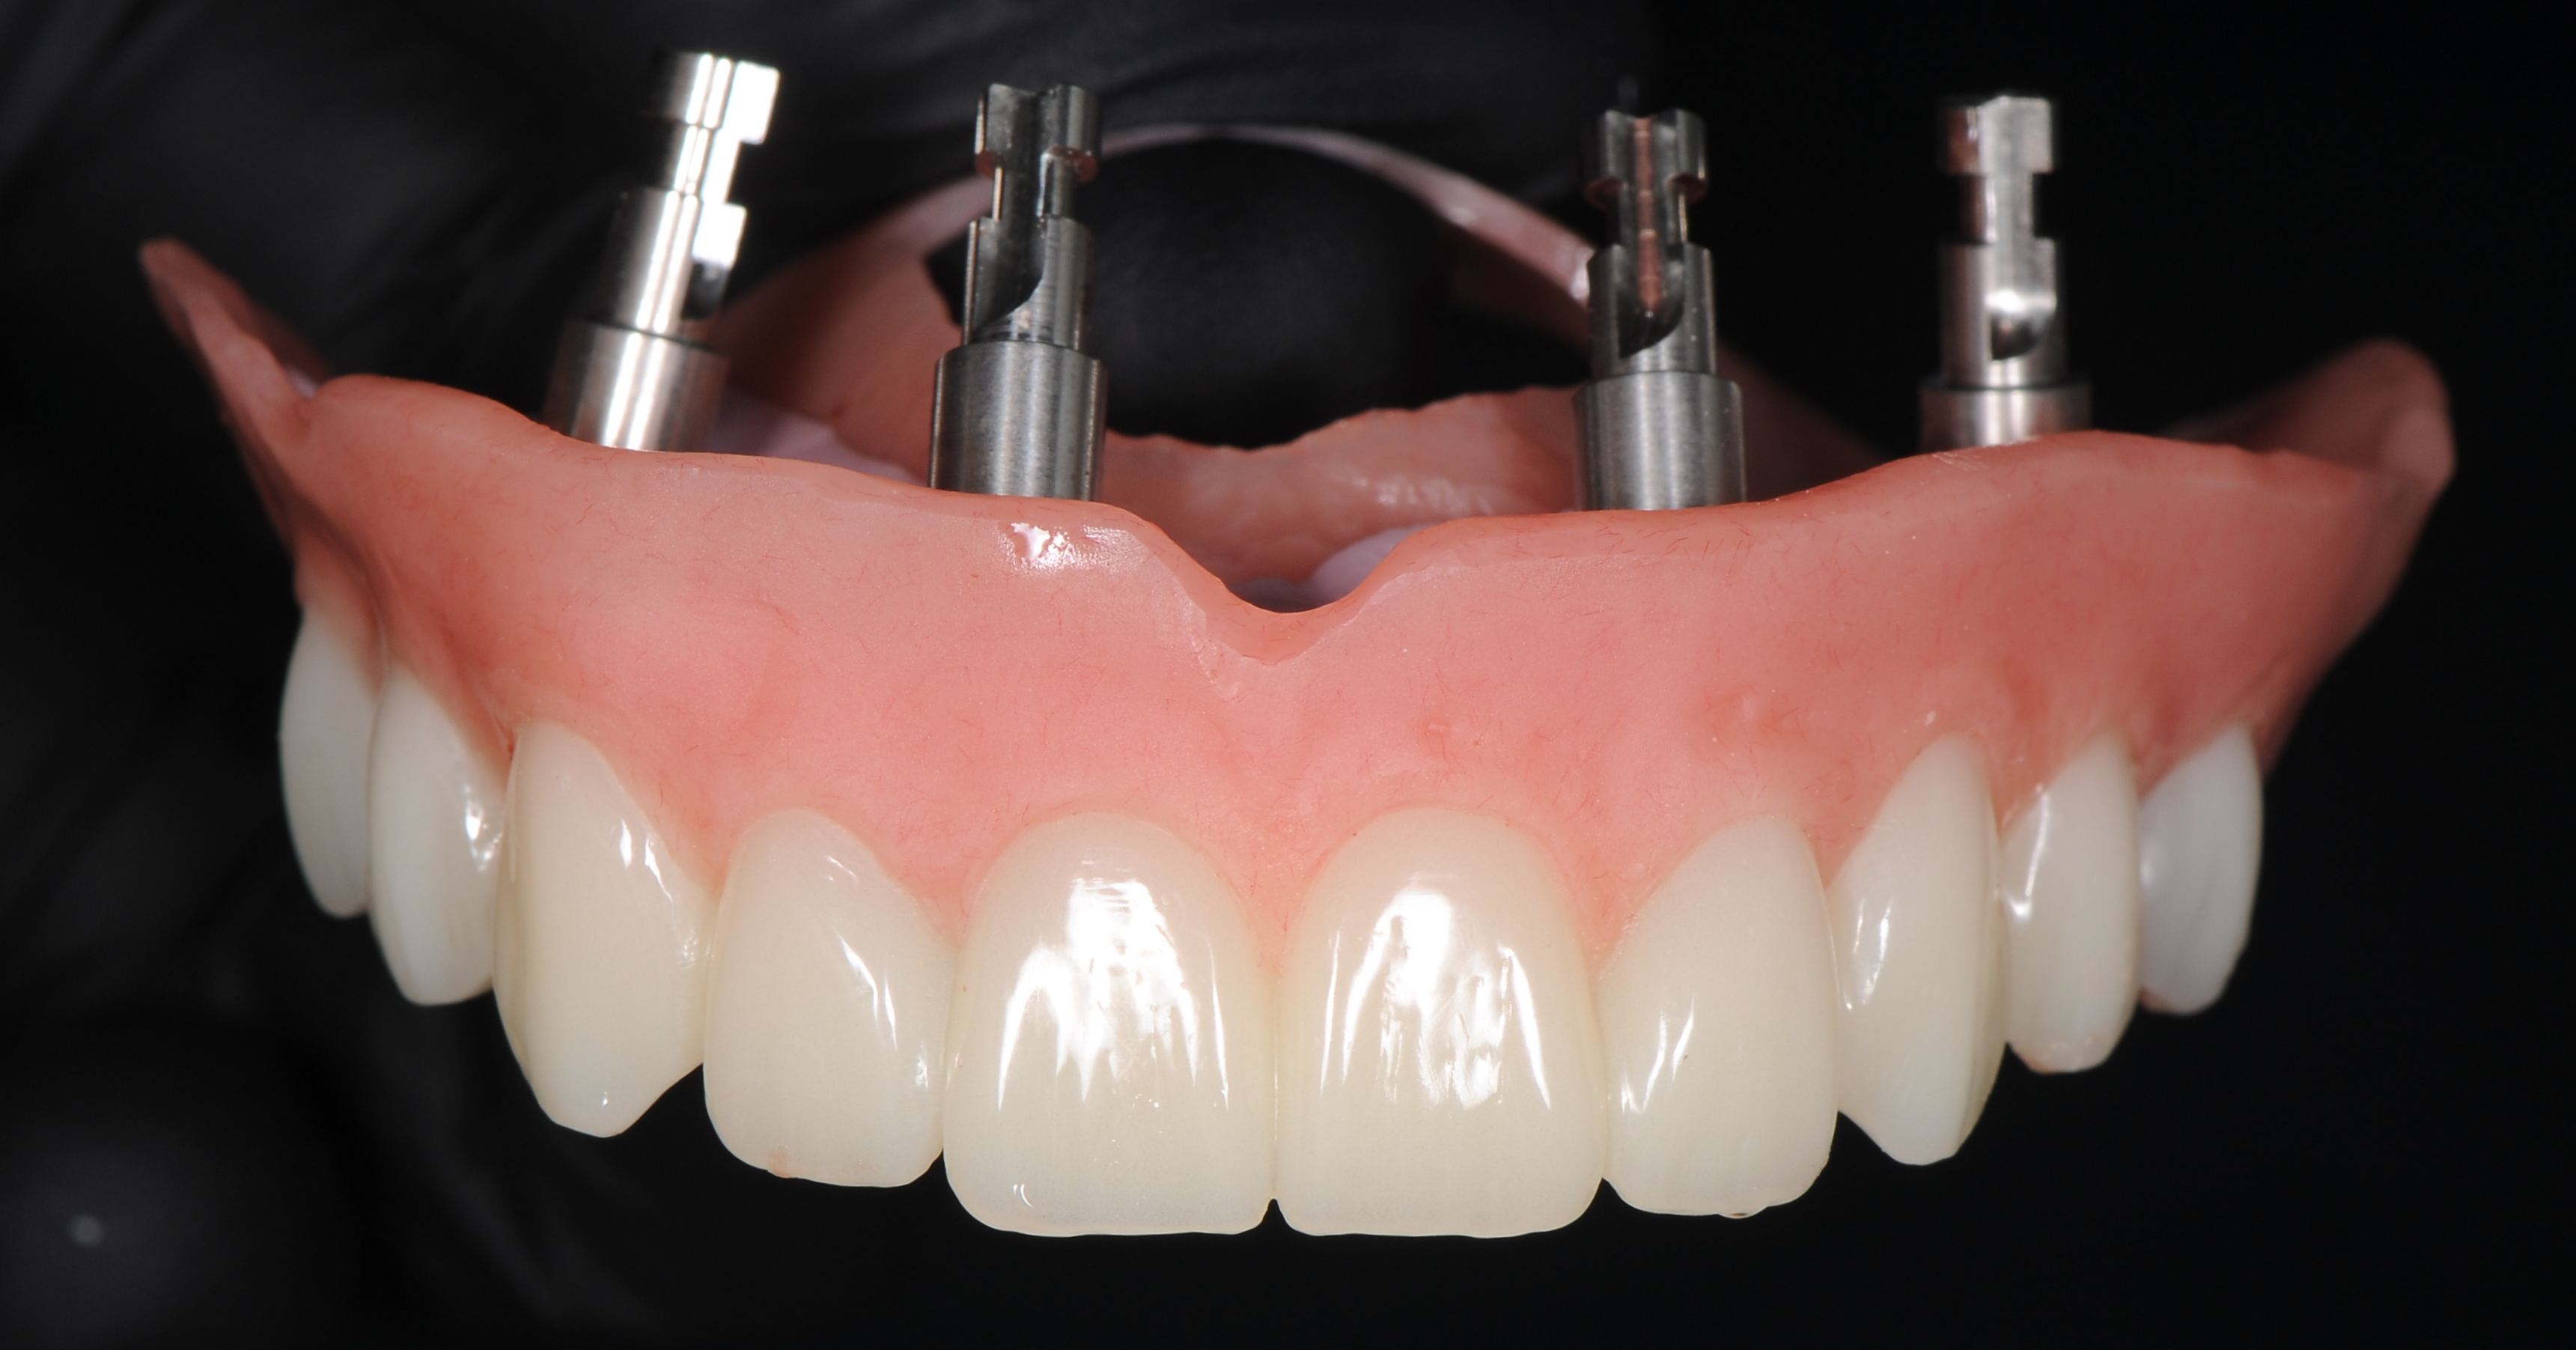

С эстетической и функциональной точки зрения провели диагностические оценочные манипуляции, согласовали с пациентом форму и цвет будущих зубов постоянной конструкции. Был изготовлен титановый фрезерованный каркас с индивидуальными абатментами NobelProcera® (рис. 44), с последующим изготовлением коронок из Диоксид циркония и имитацией розовой десны (рис. 45).

Через 8 месяцев после имплантации была зафиксирована несъёмная мостовидная керамическая конструкция с титановым каркасом по методике «All – on – 4» (рис. 46).